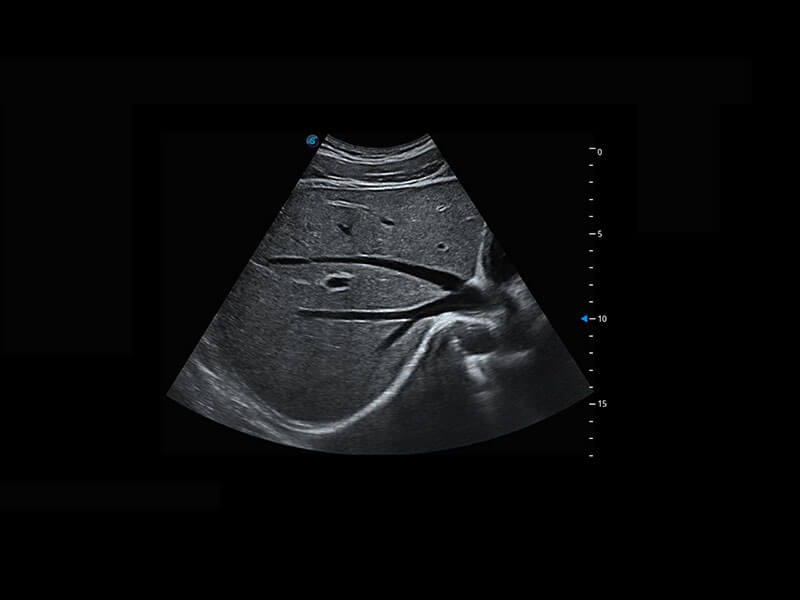

P60優(yōu)異的圖像質(zhì)量搭載專(zhuān)科探頭,在婦科基礎(chǔ)疾病的診斷、卵泡生長(zhǎng)的監(jiān)測(cè)、輸卵管通暢情況的判別等方面為您提供生殖應(yīng)用方案。

腔內(nèi)婦科-宮腔分離

腔內(nèi)婦科-卵巢